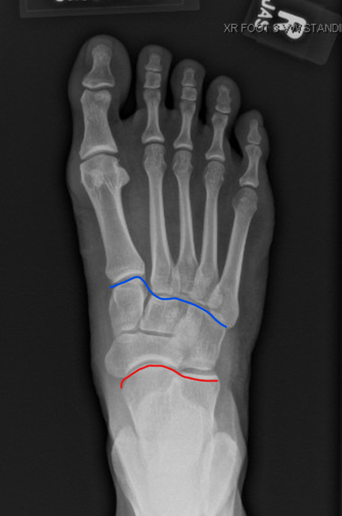

Figure 1: The blue line separates the

forefoot from the midfoot. The red line

separates the midfoot from the hindfoot.

The foot usually consists of 26 bones, and includes 3 distinct parts:

The hind foot is comprised of two bones, the talus bone which connects to the bones of the lower leg, and the calcaneus bone which forms the heel.

The midfoot is comprised of the navicular, cuboid, and three cuneiform bones.

The forefoot is comprised of five metatarsal bones and 14 toe bones called phalanges.

The hind foot is separated from the midfoot by the transverse tarsal joint, also known as the Chopart joint. This includes the talonavicular joint as well as the calcaneocuboid joints. The midfoot is separated from the forefoot by the Lisfranc joint. The Lisfranc joint separates the five metatarsal bones from the three cuneiform bones and the cuboid bone.